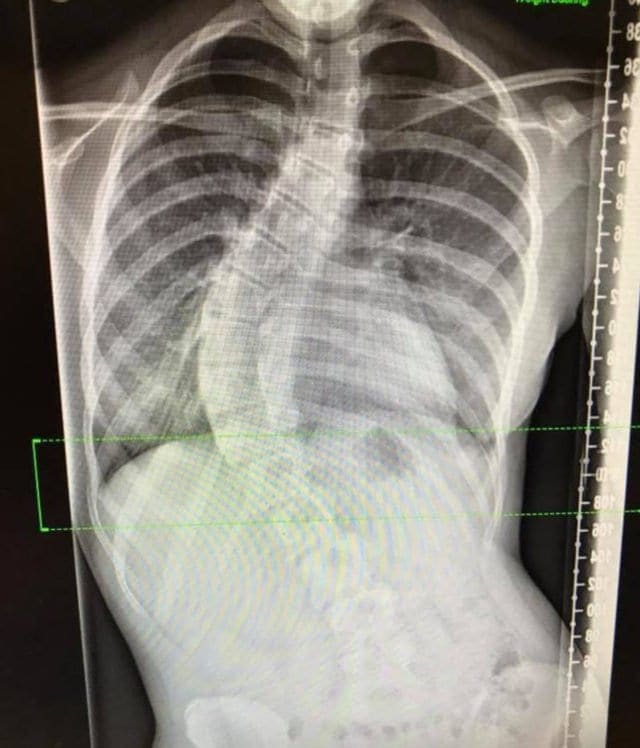

After their trip to Greece, Lily and her mother went to visit the doctor, it was time something was done about this. When they visited the doctor they were referred to a scoliosis specialist who had some bad news for Lily.

The teenager was told that eventually her spine was going to require surgery, otherwise it could lead to a deformity. While it was the last thing Lily might have wanted to hear, this was how her spine was going to be fixed, so ultimately it would be for the best.